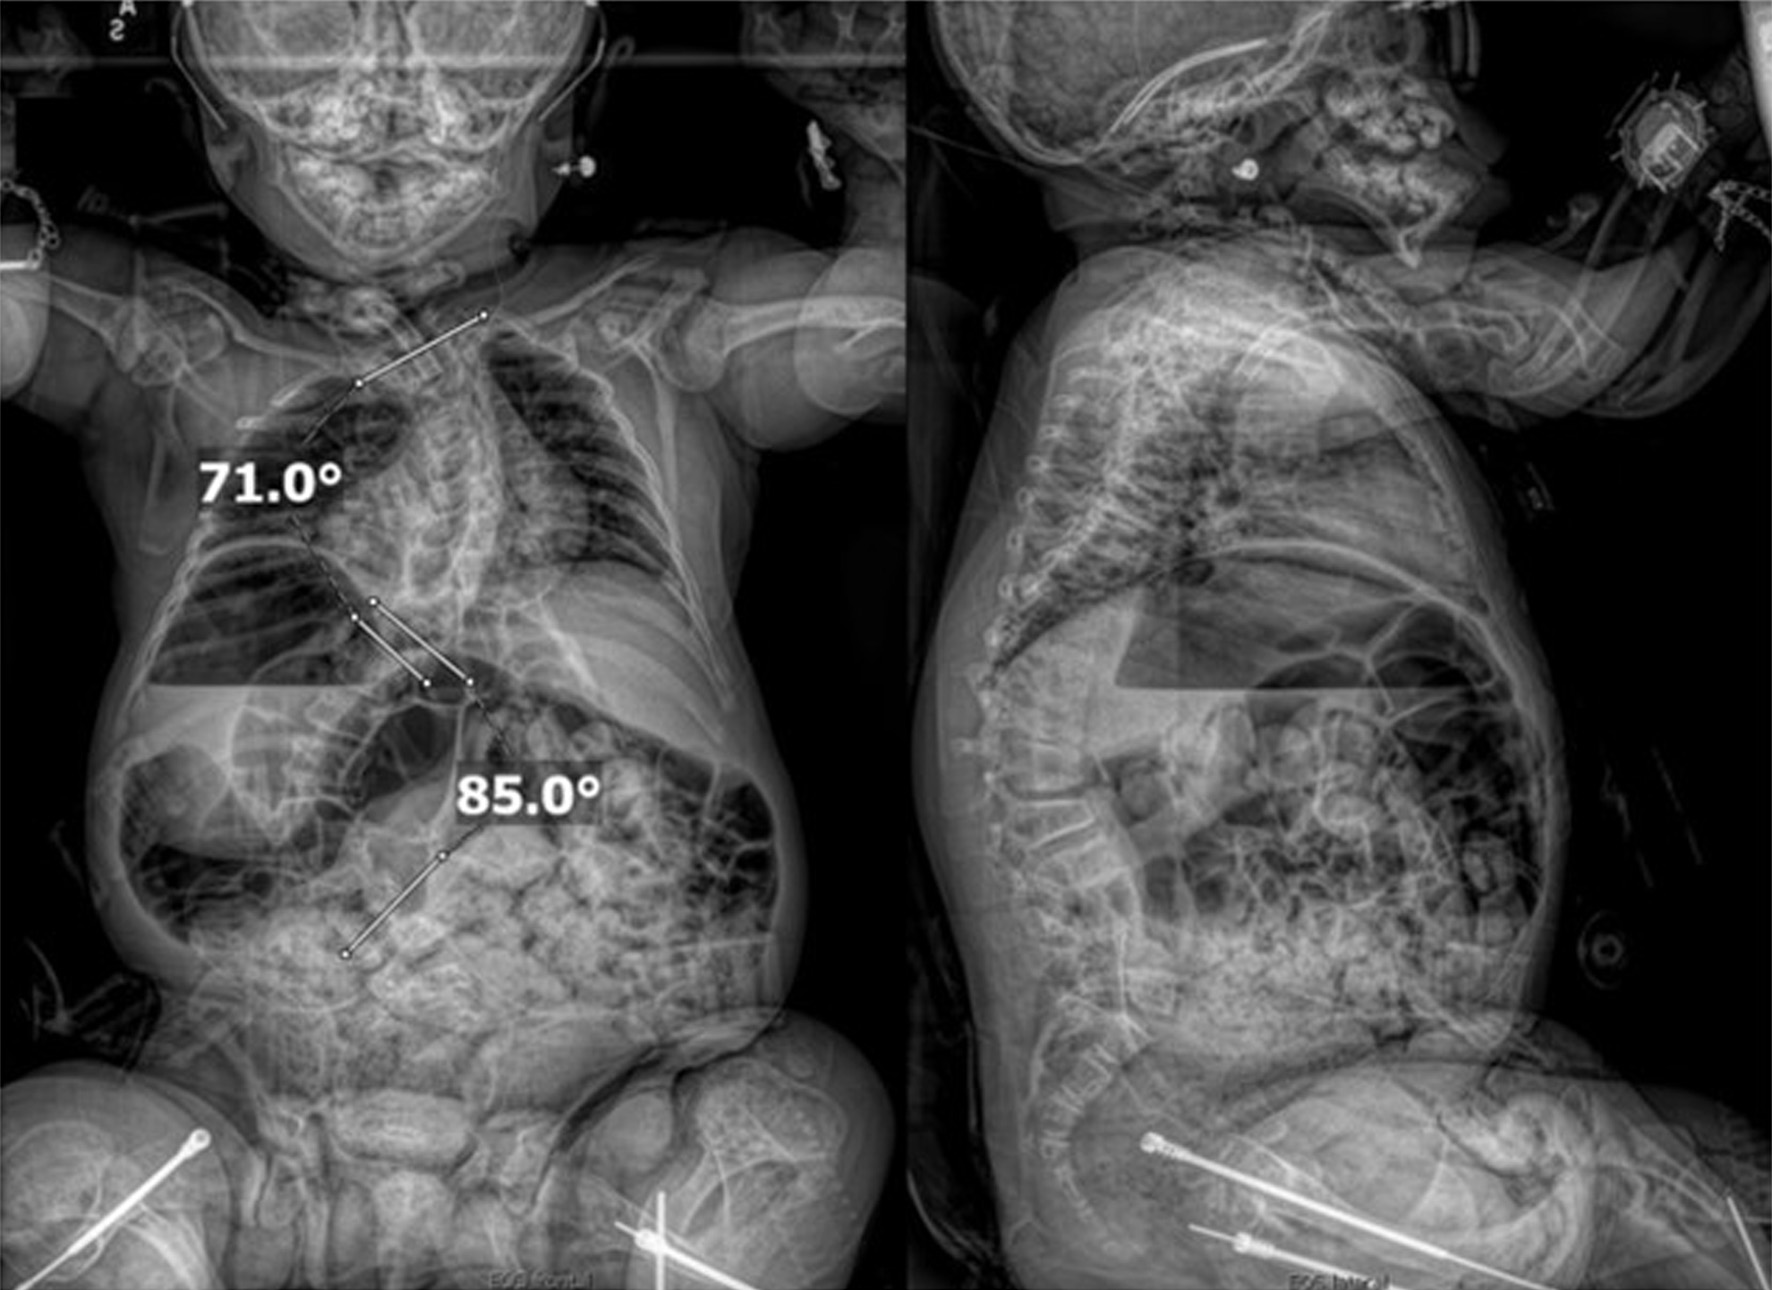

An 11-year-old male, prepubertal child with a diagnosis of OI type II and severe scoliosis presented for T2-pelvis posterior spinal instrumented fusion with posterior column osteotomies and cement vertebral screw augmentation. Preoperative evaluation revealed a 71° thoracic curve and an 85° lumbar curve (Figs 1 and 2). Despite the rarity of survival of a patient with OI type II to this age, the diagnosis was based on DNA testing which documented that the patient was heterozygous for a COL1A1 pathogenic mutation. This mutation converts a highly conserved glycine at amino acid #302 to valine. These mutations have been seen in OI types 1–4. Based on this and the clinical findings at birth, the medical geneticist specialist opined that the patient’s presentation was consistent with OI type II and that no further genetic evaluation was needed. Additional complex past medical history included Chiari I malformation, hydrocephalus status post ventriculoperitoneal (VP) shunt, restrictive lung disease, and chronic tracheostomy with ventilator dependence. The patient also had bowel and bladder incontinence, and a history of multiple long-bone fractures requiring prior orthopedic interventions, including bilateral tibial and femoral osteotomies. Growth parameters were significantly low with a weight of 15.8 kg and height of 90 cm, both below the first percentile for age. The diagnosis of OI was first suspected prenatally when a 20-week ultrasound revealed skeletal anomalies. Delivery was at term via scheduled cesarean section to a 30-year-old mother (G2P1). At birth, the neonate required oxygen supplementation and stimulation for resuscitation, with Apgar scores of 1, 4, and 8 at 1, 5, and 10 min, respectively. Early postnatal imaging showed multiple rib fractures, bowing of long bones, and deformities of the clavicle and femur, consistent with severe OI. Genetic analysis subsequently confirmed the diagnosis of OI type II, identifying a heterozygous COL1A1 pathogenic mutation (c.905G>T) resulting in substitution of glycine with valine at position 302—a mutation known to cause OI types I–IV. Following birth, the infant exhibited respiratory failure due to pulmonary hypoplasia and multiple rib fractures, leading to early ventilator dependence. At 4 months of age, a tracheostomy was performed due to progressive and continued respiratory failure and chronic ventilator dependence. Subsequently, hydrocephalus and Chiari I malformation were identified on magnetic resonance imaging that required placement of a VP shunt. The past surgical history revealed multiple surgical interventions to treat the multisystem effects of OI. These included placement of a feeding gastrostomy, circumcision, tracheostomy, and VP shunt. Orthopedic management involved bilateral tibial osteoplasties with intramedullary rodding and a left tibia and fibula osteotomy with fixation. All previous surgeries were performed under general anesthesia without complications. Current medications included nebulized albuterol every 6 h as needed; cetirizine 10 mg once a day as needed for allergy symptoms; nebulized sodium chloride 0.9% every 4 h as needed for secretion management; calcium carbonate suspension (500 mg (twice a day). Additionally, to promote bone health, a bisphosphonate infusion (zoledronic acid 0.05 mg/kg) was provided every 12 weeks. The bowel regimen included polyethylene oral powder via the gastrostomy tube, enteral sennosides, and glycerin or bisacodyl suppositories as needed. Management of chronic pain included alternating doses of acetaminophen and ibuprofen as needed. Current allergies included pork-derived products, adhesive tape, and environmental allergens. Nutrition was maintained with Boost Kid Essentials oral supplement. Pre-anesthetic physical examination revealed a young child who was tracheostomy and ventilator dependent. Ventilator support was provided by a Trilogy home ventilator. Settings include peak inspiratory pressure 24 cm H2O, positive end expiratory pressure (PEEP) 8 cm H2O, pressure support 16 cm H2O, rate 10 breaths/min with oxygen 0.5–1 L/min as needed to maintain the oxygen saturation. Breath sounds were clear. The cardiovascular examination was unremarkable with a heart rate of 100–110 beats/min. A blood pressure was not obtained due to bone fragility concerns. Preoperative complete blood count and coagulation profile were within normal limits. Additional preoperative laboratory values revealed serum calcium 7.4 mg/dL (normal 8–10 mg/dL), phosphorous 3.8 mg/dL (normal 3.7–5.6 mg/dL), and alkaline phosphatase 115 U/L (normal 137–424 U/L). Preoperative echocardiogram revealed mild pulmonary regurgitation and a patent foramen ovale. Given his severe OI and associated comorbidities, anesthetic planning emphasized fracture prevention during positioning, maintenance of normothermia, careful airway and ventilatory management through the tracheostomy, and readiness for significant blood loss. The patient was assigned an American Society of Anesthesiologists’ (ASA) physical classification IV due to severe systemic disease and ventilator dependence. Multidisciplinary coordination between anesthesiology, orthopedic surgery, pulmonology, and critical care teams was arranged, with plans for postoperative pediatric intensive care unit (PICU) admission for ventilatory and hemodynamic support and monitoring. Pre-medication included aprepitant to prevent postoperative nausea and vomiting as well as gabapentin as part of our usual postoperative pain management regimen. The patient was held nil per os after midnight and transported to the operating room where routine ASA monitors were placed. Anesthesia was induced by the inhalation of incremental concentrations sevoflurane in 50% oxygen and nitrous oxide through the existing tracheostomy. After the induction of anesthesia, two peripheral intravenous cannulas were placed (18 and 18 gauge) with a loosely placed tourniquet to facility identification of the veins. A left ulnar arterial cannula was placed with ultrasound guidance following a negative Allen’s test. A urinary catheter with a core temperature probe was inserted. Maintenance anesthesia included our routine practice to facilitate intraoperative neurophysiologic monitoring. This included total intravenous anesthesia with propofol (50–150 µg/kg/min) and remimazolam (5–10 µg/kg/min) titrated to maintain the bispectral index at 50–60, methadone (0.15 mg/kg) and remifentanil (0.1–0.3 µg/kg/min) adjusted according to the mean arterial pressure (MAP), and lidocaine (1 mg/kg/h). Intraoperative mechanical ventilation was provided by a pressure-regulated, volume-guaranteed mode with a tidal volume of 8 mL/kg and PEEP 5 cm H2O. The rate was adjusted to maintain the ETCO2 between 35 and 40 mm Hg and the FiO2 was adjusted to maintain the oxygen saturation greater than 95%. Prophylaxis against surgical site infection included cefazolin 50 mg/kg every 3 h and a single dose of gentamicin (5 mg/kg). Limitation of the needed for allogeneic transfusions included maintenance of the MAP at 55–65 mm Hg, intraoperative cell saver, a single dose of desmopressin (0.15 units/kg), desmopressin (0.15 µg/kg), and tranexamic acid infusion (50 mg/kg followed by an intraoperative infusion at 5 mg/kg/h). After instrumentation, the MAP was increased as needed by a phenylephrine infusion (0.5–1 µg/kg/min). Intraoperative temperature was managed using a forced air warming device. Prone positioning was performed cautiously and carefully, with meticulous attention to protecting pressure points, securing the airway and maintaining spinal alignment throughout positioning. The patient’s existing right frontal VP shunt was identified and protected throughout positioning. Intraoperative fluids included Normosol-R (850 mL), 5% albumin (250 mL), and a unit of packed red blood cells (320 mL). Urine output was 520 mL with an estimated blood loss of 600 mL. The surgical procedure included posterior spinal fusion with instrumentation from T2 to the pelvis with cemented vertebral screw augmentation (n = 22) from T2–L1 on the right and at T2, T4, T5, T7–11, and L3–4 on the left with posterior column osteotomies from L11–T2. After completion of the 11-h surgical procedure, the patient was turned supine, and ventilation was maintained through the tracheostomy with a patent, unobstructed airway. The cardiovascular status remained stable. The patient was awake, responsive, and followed commands. There were no complaints of pain or nausea. The patient was transported directly from the operating room to the PICU with the anesthesia team in attendance. Postoperative pain was managed with intermittent acetaminophen, a lidocaine infusion, and morphine delivered by nurse-controlled analgesia, which was subsequently transitioned to oral acetaminophen, ibuprofen, valium, and oxycodone managed under the guidance of the pain service. Physical and occupational therapy were involved throughout the hospital stay. Postoperative imaging showed well-aligned spinal instrumentation without concerns (Fig. 3). Routine home medications were restarted. The remainder of the postoperative course was uneventful, and he was discharged home on postoperative day 5. Follow-up at 3 months postoperatively with radiographic imaging demonstrated overall appropriate alignment and positioning of all hardware.

Figure 1. Preoperative seated radiographs demonstrating severe scoliosis with 71° right thoracic curve (T1-T9), 85° left lumbar curve (T9-L3, major), and thoracolumbar kyphosis.